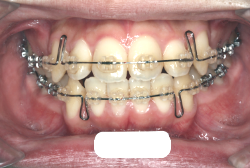

過蓋咬合

過蓋(かがい)咬合とは、奥歯を閉じた時に前歯が深く咬み込み、下の前歯がほとんど見えなくなるくらい閉じすぎになる症状です。強く咬んでいると言うことは、力が強く出て一見良さそうに聞こえますが、深く咬みすぎることは歯にも良くないですし、口腔周囲の環境としても好ましくない状態です。

深く咬みすぎると、歯と歯で接触しながら閉じる距離と面積が広範囲にわたりすぎ、必要以上に歯をすり減らします。また顎の関節の自由な動きを歯と歯の接触関係が必要以上に規制してしまうため、顎の関節の動きがだんだん悪くなり、顎が開きにくくなったり、開いていく途中で大きな音が出たり、ひどいときには途中からそれ以上開けなくなったりします。こういう症状を"顎関節症"と言いますが、こういう状態にもっともなり易い咬み合わせです。顎関節症は、中年期以上にある日突然症状が発現することが多く、一度発症するとなかなか健康な状態にならない、消耗性の病気です。若くて抵抗力のあるうちはまだ良いのですが、過蓋咬合の人は歯がすり減りやすく、時間の経過とともに、ますます咬み合わせが深くなっていく傾向があり、早期発見・早期治療が望まれます。

「歯並びの凸凹を直したい」という主訴で来院したケースです。診断の結果、たしかに「叢生」という隙間が足りないと言うことが原因の凸凹症例でした。

しかし、それ以上に問題なのは「前歯の噛み合い方が深すぎる」という症状で、初診の歯の正面写真を見ると下の前歯が全く見えません。こういう症状を矯正学では「過蓋咬合(かがいこうごう)」と言います。過蓋咬合を放置すると、将来的に顎関節に悪影響を与えるとされており、顎関節症の原因因子の一つです。また下の前歯の先端が、上の前歯の裏側の歯茎と強く接触するため、歯周病の原因にもなります。

検査の結果、凸凹が軽症なため非抜歯で矯正すること可能と判断、マルチブラケット装置にて治療しました。治療後は歯並びが綺麗になっただけでなく、噛み合わせ的にも正しい状態が確立しています。